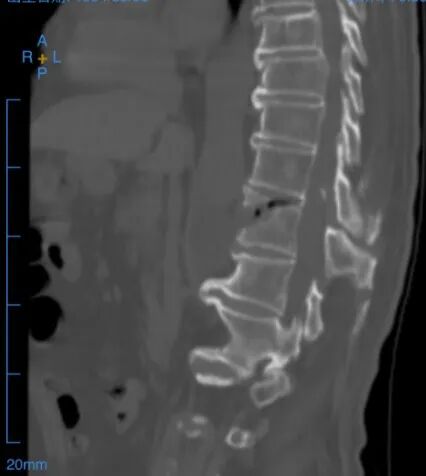

此次正逢中南大学湘雅医院脊柱外科专家邓盎教授来湘潭市中医医院坐诊,患者慕名前来。邓盎通过详细询问病史、体格检查,并结合脊柱CT、MRI等影像学检查结果,明确诊断患者为胸椎Chance骨折保守治疗不愈合、胸椎黄韧带骨化,胸椎椎管狭窄。

为确保手术安全、有效开展,最大限度降低手术风险,邓盎高度重视,第一时间结合患者病情资料进行全面分析,并与湘潭市中医医院骨科团队共同研讨,制定个性化手术方案,明确手术流程、关键操作要点及围手术期风险防控措施,为手术成功奠定坚实基础。

手术当天,邓盎走进手术室,全程指导手术操作。湘潭市中医医院骨科团队与麻醉科、手术室等相关科室紧密配合,严格按照预设方案,精准实施脊柱骨折固定、植骨融合及黄韧带骨化灶清除等操作。术中,邓盎凭借丰富的临床经验和精湛的手术技巧,精准处理每一个操作细节,有效避开脊髓、神经根等重要组织,最大限度减少手术创伤;湘潭市中医医院团队默契配合,熟练完成各项辅助操作,确保手术有条不紊推进。整个手术过程顺利,历时3个多小时,术中患者出血少、无任何并发症发生。

手术固定情况